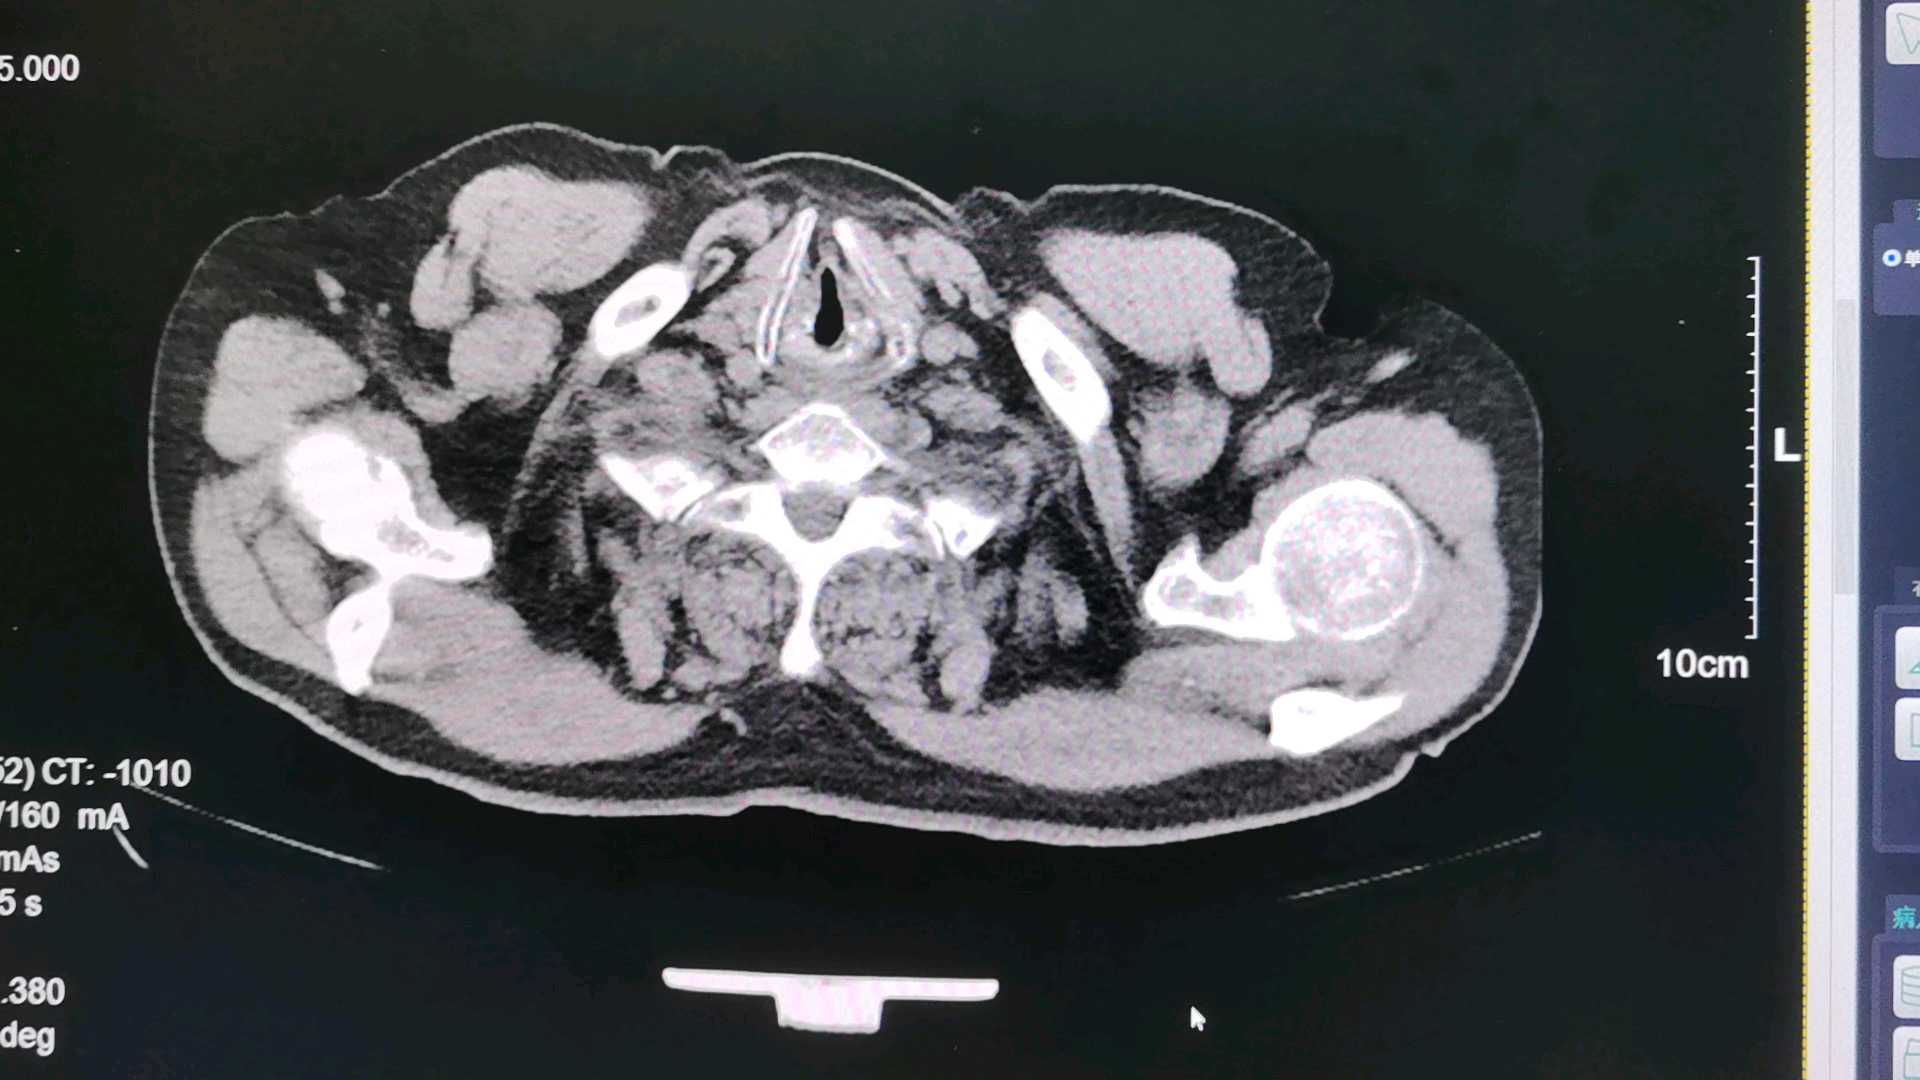

病例患者男 73岁,胸闷,胸痛许久,抗炎治疗一周后复查,来科室做的胸部CT。

患者男 73岁,胸闷,胸痛许久,抗炎治疗一周后复查,来科室做的胸部CT。

想请问老师,这是肺气肿啊!还是肺大泡